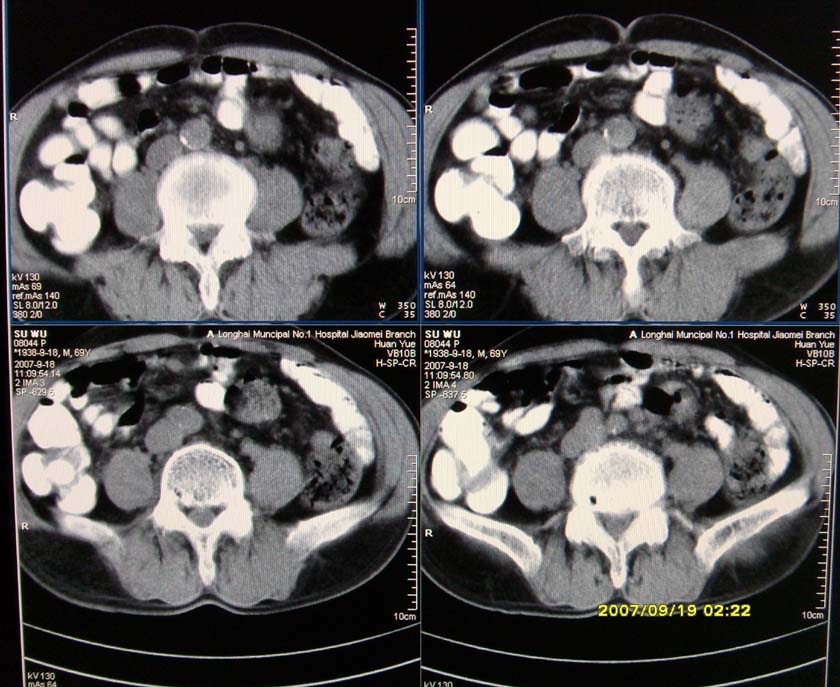

以下是引用xclzq_910在2007-9-19 16:58:00的发言:[br]直肠壁增厚,管腔偏移,直肠癌可能性大

以下是引用宝天曼在2007-9-19 21:11:00的发言:[br]根据直肠壁不规则增厚,考虑直肠肿瘤,不过最后的确诊还是需要肠镜.